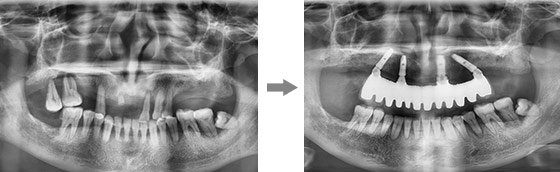

康贝佳胡主任为李大爷做了详细的口腔检查,并采用了ALL-ON-4技术,整个手术过程仅仅30分钟,只需4颗植体就恢复了半口牙,不仅创伤小、疼痛轻,恢复快,且为李大爷省了近一半的费用。

对于年纪较大、体弱、半全口缺牙中老年人来说,采用ALL-ON-4微创即刻用种植技术,采用斜拉式力学设计利用多个天然承重点,4颗牙根便可承受来自多方向的力即可恢复半口牙,在骨量严重萎缩的情况下,也无需植骨。并且甚至可以实现当天种植当天用,同时节省至少1/3的费用。

从术前诊断、手术种植、术后修复等一体化流程,通过口腔数字全景检查和CT片、牙槽骨条件测量、三维模拟种植、血常规检查,制定个性化专属种牙方案,根据缺牙老人的时间、费用、年纪多方面综合考虑,做到让缺牙老人放心种牙,满意种牙。